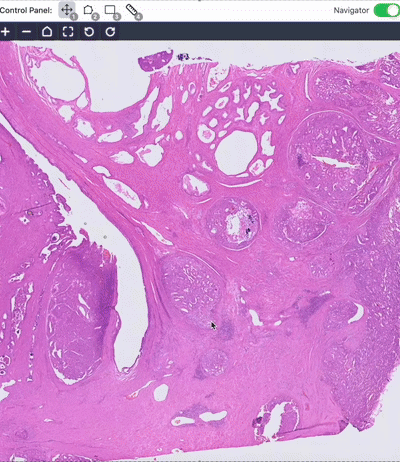

2. AI Systems and Human-AI Collaboration

We develop AI software platforms to assist human experts in clinical practice, promote human-AI collaboration. We also optimize LLMs.

TissueLab: A co-evolving agentic AI system for medical image analysis

Songhao Li, Jonathan Xu, Tiancheng Bao, Yuxuan Liu, Yuchen Liu, Yihang Liu, Lilin Wang, Wenhui Lei, Sheng Wang, Yinuo Xu, Yan Cui, Jialu Yao, Shunsuke Koga, Zhi Huang

Arxiv (2025)

TissueLab web portal [website] []

A pathologist–AI collaboration framework for enhancing diagnostic accuracies and efficiencies

Zhi Huang, Eric Yang, Jeanne Shen, Dita Gratzinger, ..., Thomas J. Montine & James Zou

Nature Biomedical Engineering (2024), cover article

nuclei.io: AI platform for digital pathology [website] []